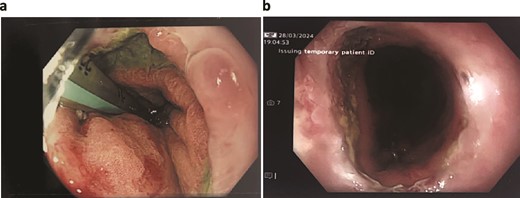

On day 2 post-diagnosis, the patient underwent an OGD, VACStent insertion, and ultrasound-guided pleural drain placement. The endoscopy revealed a 2 cm linear defect in the lower oesophagus just above the gastroesophageal junction (Fig. 3), and the VACStent was connected to 125 mmHg of negative pressure, confirming appropriate positioning. The patient tolerated the procedure well without intraoperative complications and was transferred to the ICU intubated.

Patient Three: Before VACStent insertion, showing the oesophageal defect.